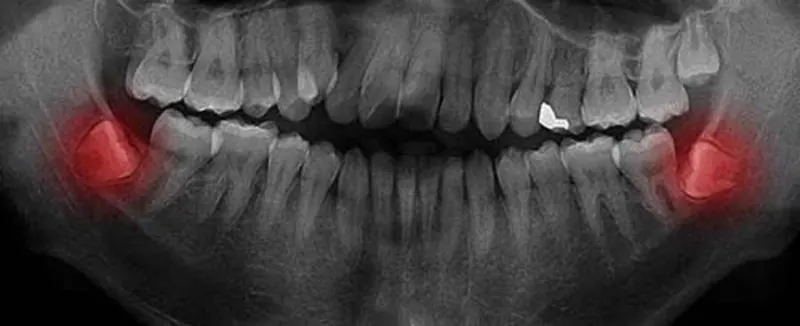

Extracción de terceros molares, colocación de implantes y cirugías con enfoque conservador.

• Especialista en Cirugía Bucal

• Experta en extracción de muelas del juicio e implantología